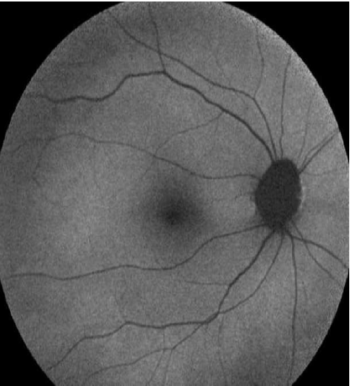

Figure 6: FAF image. Normal control

View Figure 6

No change in FAF was detected in the control group (Figure 8). Since curcumin binded to Bamyloid, it was possible to see hyperintense dot like changes on FAF. This proved that the lesions consisted of beta amyloid.The roundish lesions on OCT also became more prominent. In 26 patients, more than 10 curcumin stained lesions were seen and this was considered as moderate disease.